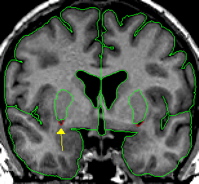

|  | The putamen is a subdivision of the lenticular nucleus (the other division is the pallidum). The lenticular nucleus from the axial view resembles a rounded triangle that is divided into two major sections. The putamen is the lateral part of this triangle.The putamen starts small and ends small in the coronal view. The putamen quickly grows to its greatest size in the middle and in the medial posterior portion it closely resembles a goldfish shape. The putamen lies lateral and partially anterior to the thalamus. It is bordered laterally, superiorly, and inferiorly by white matter. The putamen is usually bordered medially by the pallidum. When the pallidum is not yet present or has already disappeared the putamen is bordered medially by the internal capsule. | |

| Part II - Blood vessels There is often a blood vessel near the inferior border of the putamen, this should not be included as part of putamen. The vessel should be extracted separately using a contour line and labeled "vessel." The vessel will serve as at least a portion of the inferior border. | ||

| Labeling The final outline should be labeled as "putamen," and any blood vessels extracted should be labeled as "vessel." | ||